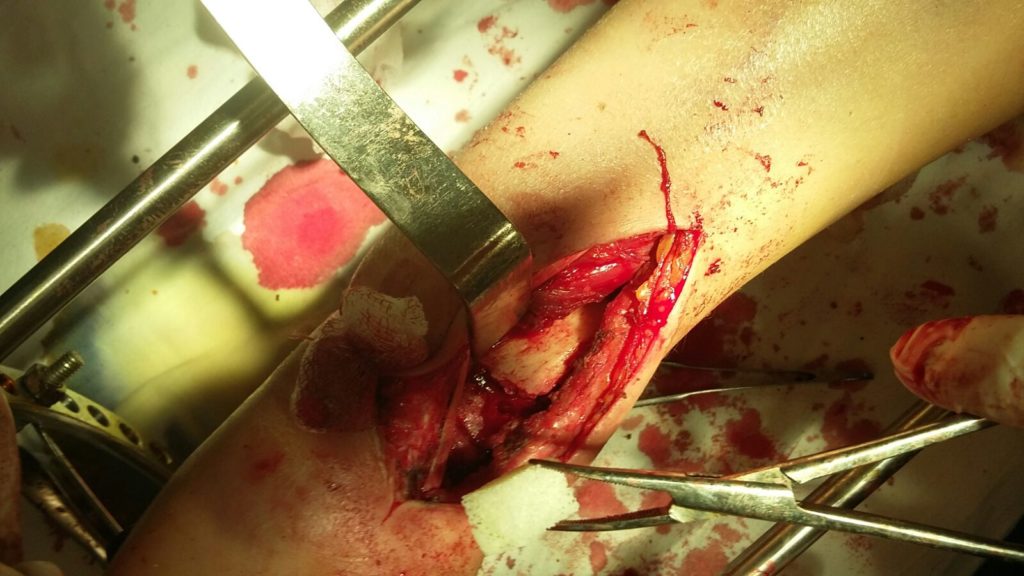

Операция - открытая репозиция, остеосинтез лучевой кости пластиной с костной ксенопластикой материалом "Остеоматрикс". На контрольных снимках в три месяца имеется консолидация перелома, миграции фиксатора нет, имеется остеоинтеграция ксенопластического материала.